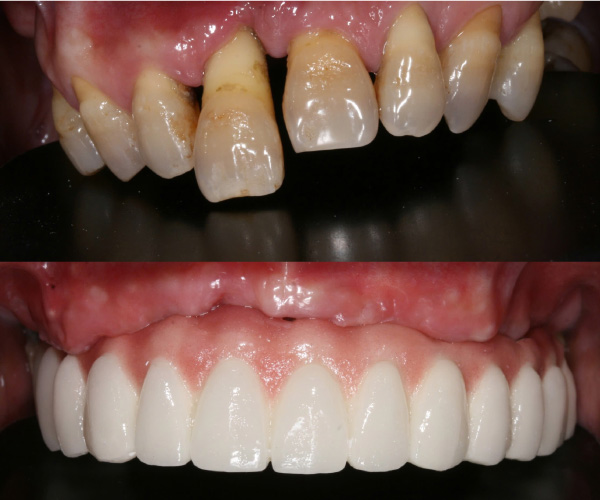

Cấy ghép implant phục hồi toàn diện chức năng nhai và thẩm mỹ cho người bị nha chu nghiêm trọng, người mất răng toàn bộ và người cao tuổi nhiều bệnh nền.

Tiến sĩ, Bác sĩ Võ Văn Nhân với hơn 23 năm kinh nghiệm trong lĩnh vực Implant Nha khoa, đã thực hiện thành công hơn 20.000 ca cấy ghép răng Implant từ đơn giản đến phức tạp. Những thành tựu đặc biệt mà Ts.Bs Võ Văn Nhân đạt được góp phần mang lại nụ cười hạnh phúc, mở ra cơ hội cho rất nhiều trường hợp mất răng, không răng bẩm sinh.